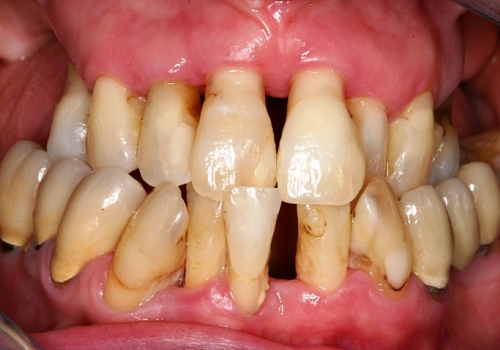

Qeyri-cərrahi parodontoloji müalicədən sonra bəzi hallarda, bu və ya digər bölgədə dərin parodontal ciblər (diş əti və sümük cibi) qalmaqda davam edir. Bu hallarda çox zaman müalicə cərrahi metodların tətbiqi ilə davam etdirilir. Bu zaman əsas məqsəd mövcud parodontal cibin bu və ya digər metodlarda aradan qaldırılmasını təmin etməkdir.

Çünki bu ciblər çox zaman pasiyent tərəfindən yetərincə təmizlənə bilmir. Bu isə həmin bölgəyə tədricən ərp və dolayısı ilə də bakteriya koloniyalarının toplanmasına səbəb olur. Bu proses yenidən yerli iltihabın ortaya çıxmasına səbəb olur. Tətbiq edilən cərrahi metodlar əsasən cibin yerləşdiyi diş bölgəsi, cibin eni, dərinliyi, konfiqurasiyası və s. xüsusiyyətlərə görə müəyyənləşdirilir. Bu zaman məqsəd mümkün olduqda həmin bölgədə bərpa prosedurunu həyata keçirmək, mümkün olmadıqda isə rezektiv müalicənin tətbiqi ilə həmin bölgəyə ərp toplanma ehtimalını azaltmaq və gigiyenik prosedurların icrasını pasiyent üçün rahatlaşdırmaqdır.